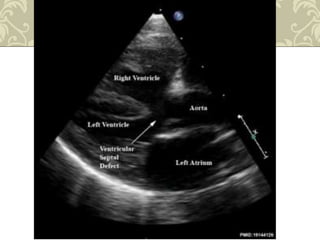

Ecocardiografia

 CIV

 Obstrução do trato de saída ventricular direita

DIAGNÓSTICO

• #23 Observar o defeito do septo e o cavalgamento da aorta